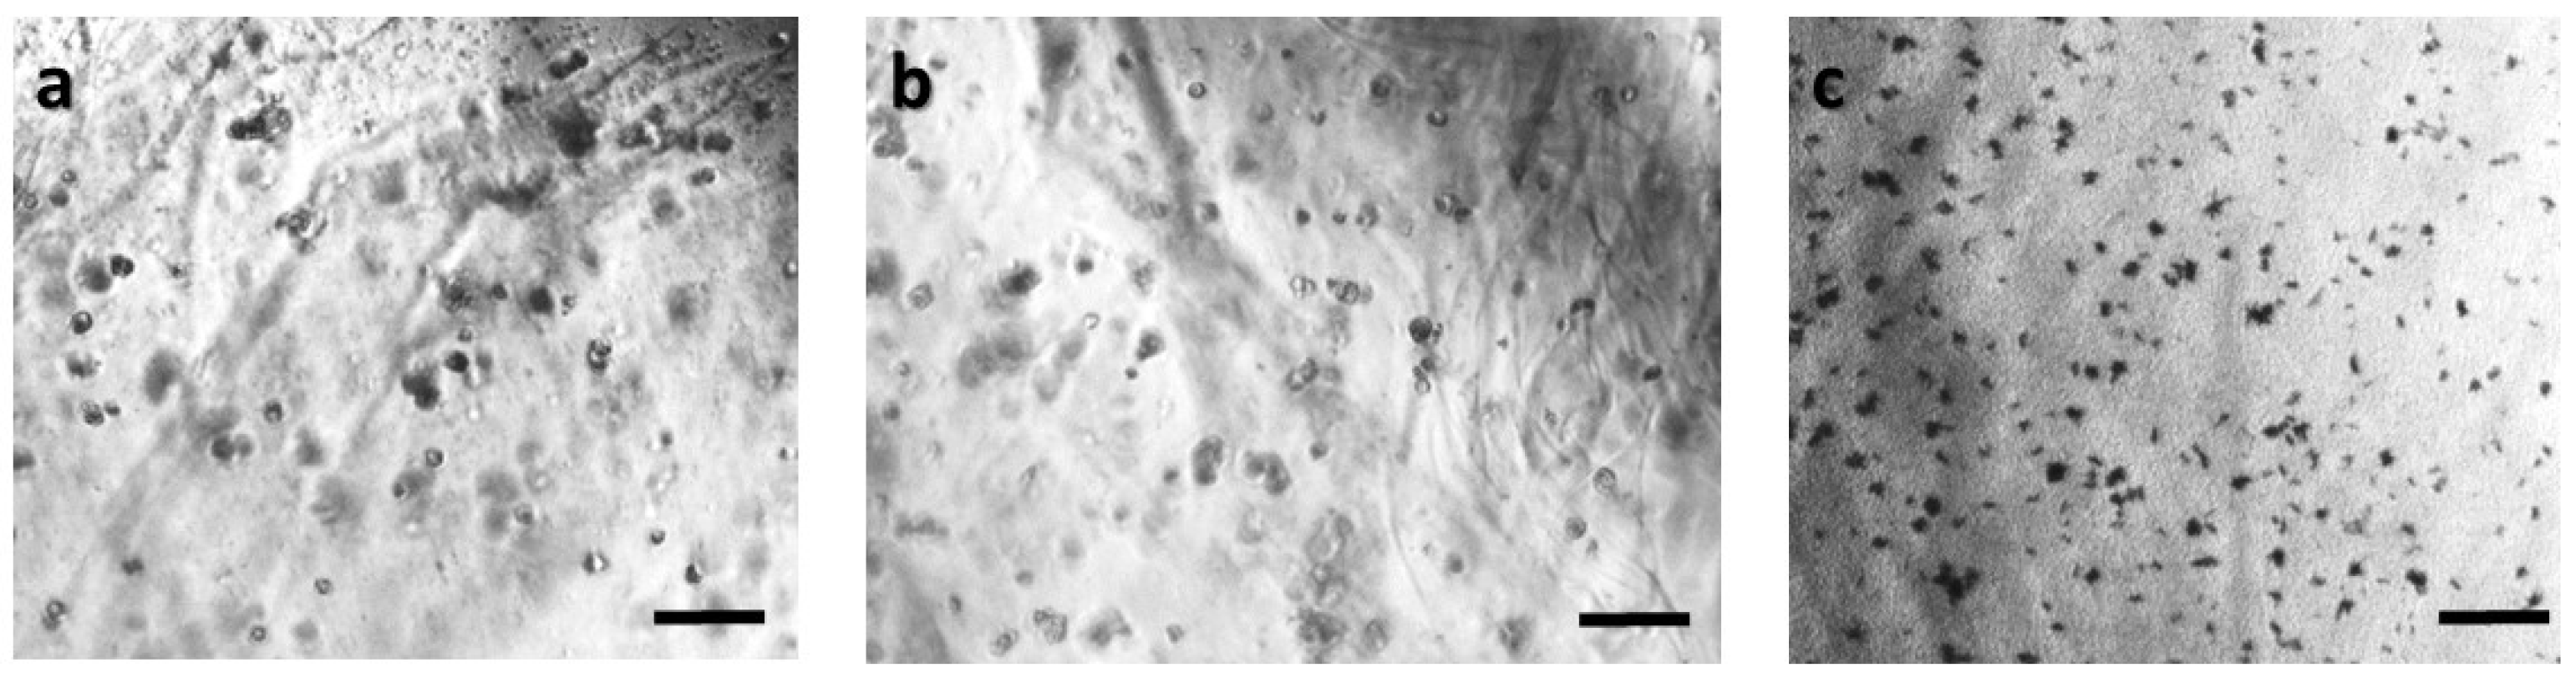

Figure 4. Panoramic view of HeLa immobilized cells in 3D matrix after treatment with MTT for 24 h showing the viability in three different population densities: (a) 50,000 cells; (b) 100,000 cells; and (c) 200,000 cells/100 μL. Scale bars = 50 μm.

In order to ensure that calcium alginate was a proper immobilization matrix for the cancer cell culture, we assessed cellular viability with the MTT uptake assay. Cells were cultured in the matrix for 24 h (with and without treatment with 5-FU), and the proliferation was determined microscopically and photometrically after MTT application. Figure 2, Figure 3, Figure 4 and Figure 5 depict the microscopic observations for three different populations of the four cell lines immobilized in calcium alginate after incubation with MTT.

Viable cells were dyed purple using the yellow formazan (MTT) by intracellular NAD(P)H-oxidoreductases [43]. We can see that cellular proliferation is affected neither by the immobilization matrix, nor by the increase in the cell population density. Contrary to this observation, the results from the photometric MTT determination presented in Figure 6, Figure 7, Figure 8 and Figure 9 showed an increase in the absorbance as cell number population densities increase, whereas the addition of 5-FU led to a significant reduction in cell viability (see Table 2) in almost all cell lines. Cell population alterations in the neuroblastoma SK-N-SH cell line (see Figure 6) appear to have a limited impact in MTT absorbance for both cell cases, i.e., treated with 5-FU and untreated. On the other hand, in the case of the remaining cell lines (Figure 7, Figure 8 and Figure 9), we observed an increase in absorbance proportional to the cell number.

An optical inverted microscope was used for the observation of the differences in cell morphology between the four different cell lines after conducting the MTT colorimetric assay [43]. Similar observations were reported for studies on epithelial cancer cells in 3D culture [61,62,63]. Our results indicated that the immobilization matrix did not affect cell viability. Furthermore, the photometric MTT determination revealed an increase in cellular proliferation relative to the cell population density. On the other hand, when the anticancer agent 5-fluorouracil (5-FU) was added to the cell medium, viability was significantly reduced, suggesting that the 3D immobilization matrix does not influence the influx of the compound in the alginate hydrogel.